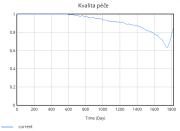

| 22:34, 15 June 2025 | 1 KvalitaPéče.png (file) |  |

11 KB | Kozo01 | 1 | |